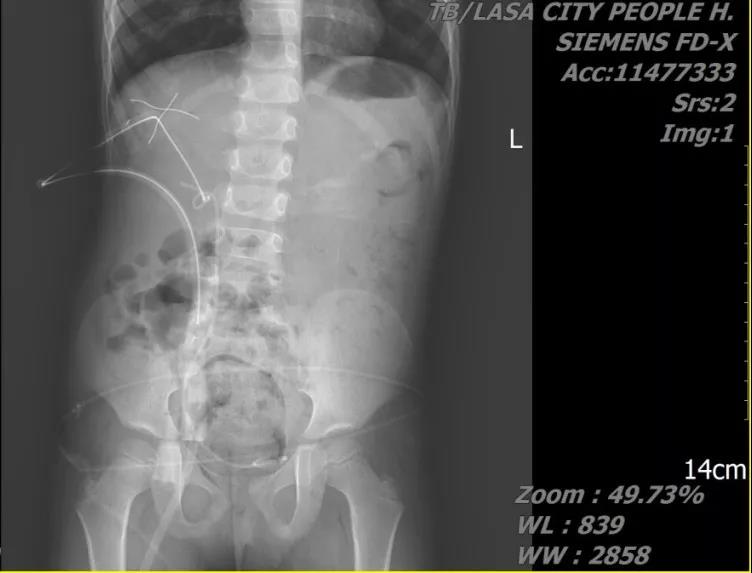

患儿,男,8月龄,主因“排尿困难伴哭闹1日”就诊。术前诊断:双肾结石;予以右侧mPCNL。

术中未留置DJ管;术后患儿愈合良好,术后第3天拔除肾造瘘管,第4天拔出尿管,第5天出院。